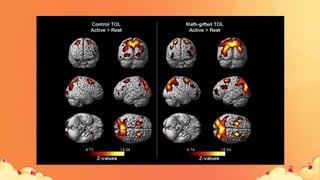

ÁreasfuncionaisdoCórtex